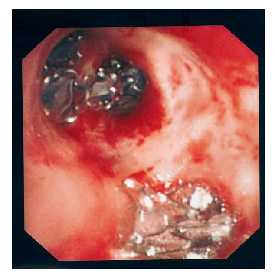

A 73 year-old man heavy smoker and ex-intravenous drug user, had history of pulmonary TB. He was admitted for acute shortness of breath. CXR revealed left pneumothorax with near-complete left lung collapse. CD was inserted with satisfactory lung expansion, but the air leak persisted. HRCT showed left pneumothorax with chest drain in-situ. There were fibrocalcific foci in the left upper lobe (LUL), diffuse emphysema, and some small bullae. Thoracic surgeon was consulted but surgical treatment was declined for the high operative risk. Flexible bronchoscopy under local anaesthesia (LA) was done on day 23. Blockage of the LUL bronchus (inclusive of the lingular segments) resulted in immediate cessation of air leak, whereas no such effect was seen when the left lower lobe (LLL) bronchus or the individual LUL segments were blocked. One EBV (Emphasys Medical Inc, California, CA) was placed to block both LB4 and LB5, and air leak continued. The second EBV was placed into LB3, and the third EBV placed into LB1, and airleak still continued. The LB3 valve was taken out and put into LB2, but air leak still continued. Finally, when a fourth EBV was put into LB3 (i.e. with all LUL segments blocked), the air leak stopped. (Fig.1)CXR on the following day showed LLL fully expanded and LUL partially collapsed. As there was no air leak, CD was removed and patient was discharged one day afterwards (day 25). During follow-up assessment, there was no recurrence of pneumothorax. Bronchoscopy was repeated 43 days after the first one and all the EBVs were removed. Subsequent CXR showed no recurrence of pneumothorax and LUL was expanded. There was progressive improvement in his general condition, with no recurrence of pneumothorax 9 months after removal of chest drain. Post bronchodilator FEV1 was 0.84L (44% predicted) and FEV1/FVC was 48%